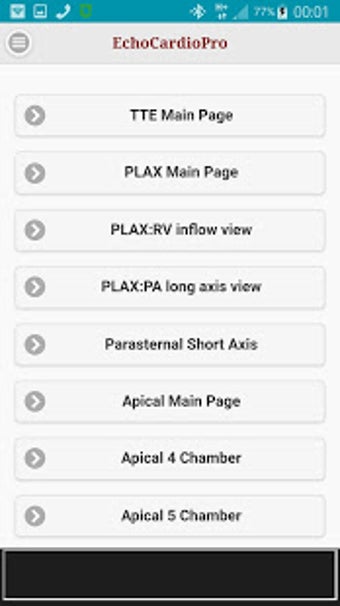

Aplikacja dostarcza kompleksowych informacji na temat echokardiografii przezklatkowej (TTE) i echokardiografii przełykowej (TEE) oraz ich odpowiednich korzyści w ocenie czynności skurczowej i rozkurczowej lewej i prawej komory, regionalnego ruchu ściany, wad zastawkowych serca i chorób osierdzia. Zawiera również szczegółowe informacje na temat różnych widoków, takich jak długoosiowy przysercowy, krótkoosiowy przysercowy, wierzchołkowy, podżebrowy, nadobojczykowy, śródprzełykowy, poprzezżołądkowy, głęboko poprzezżołądkowy i wysoko przełykowy.

Interfejs aplikacji jest przyjazny dla użytkownika, a dostarczane informacje są istotne, dokładne i aktualne. Należy jednak zauważyć, że aplikacja nie zastępuje wiedzy i doświadczenia wykwalifikowanego lekarza. Ogólnie rzecz biorąc, EchoCardioPro to doskonały towarzysz nauki i przeglądu dla profesjonalistów w dziedzinie echokardiografii.